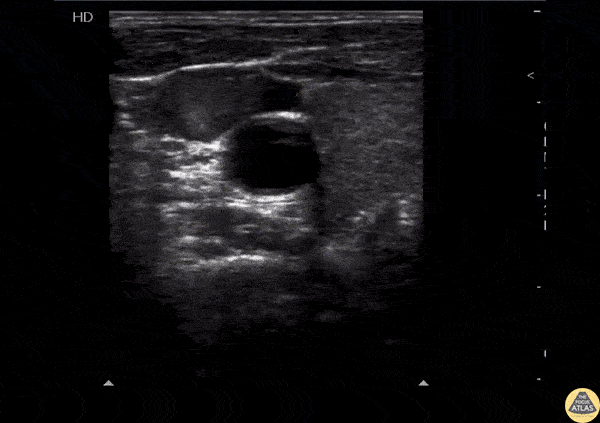

This clip shows spontaneous echo contrast (SEC) in the IJV. This finding is indicative of blood stasis and may be a precursor to thrombus formation. Image courtesy of Robert Jones DO, FACEP @RJonesSonoEM Director, Emergency Ultrasound; MetroHealth Medical Center; Professor, Case Western Reserve Medical School, Cleveland, OH View his original post here